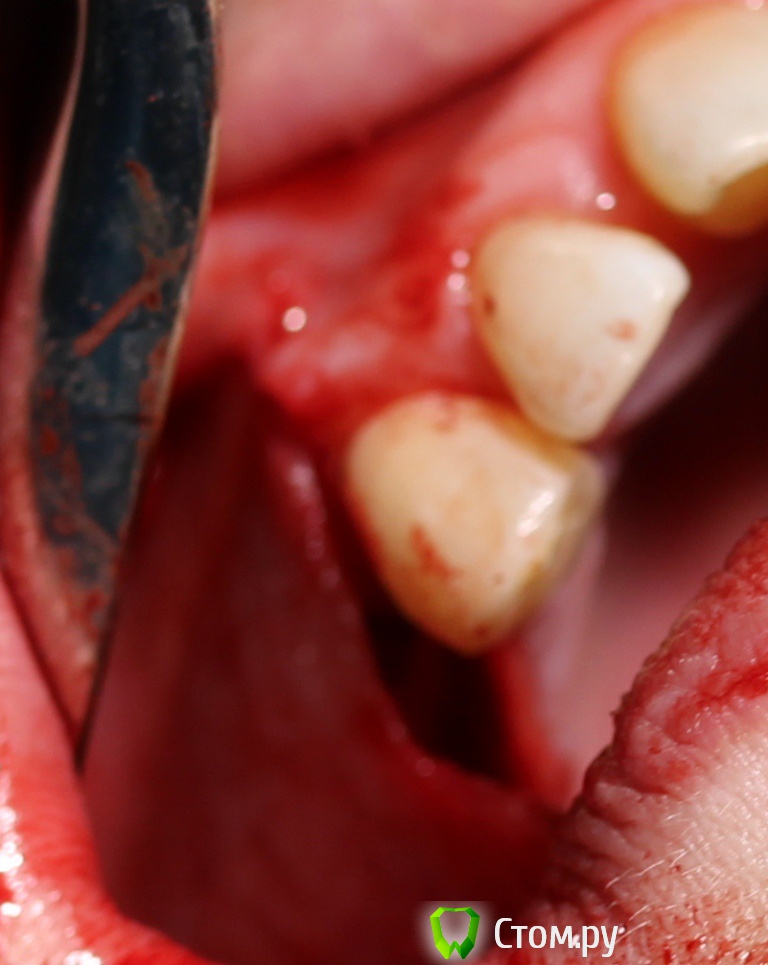

zzkz Опубликовано 18 апреля, 2014 Поделиться Опубликовано 18 апреля, 2014 Спасибо коллегам за вдохновение! Хотя есть не радующие моменты, шел на риск. Фото третьего ассистента немного размыто. Пока не получается отладить(в процессе) Синус+ Небольшое расщепление+ био осс под Ламину.Швы толстые викрил 4-0 - другого не оказалось под рукой, был Пролен 6-0(сомнения что прорежут слизистую) Из вопросов которые возникли 1. винтов не оказалось маленьких(выяснилось во время операции), пришлось фиксировать на винты длиной 10мм в графт в пазухе.что то из за этого может произойти как думаете? 2. импланты с нулевым торком(не надо было делать пропилы), рукой установил, боялся даже заглушку сильно крутить? не чревато ли? 3. Импланты вроде ставил параллельно, а на снимке корявенько, панорамник что ли врет? 1 Ссылка на комментарий